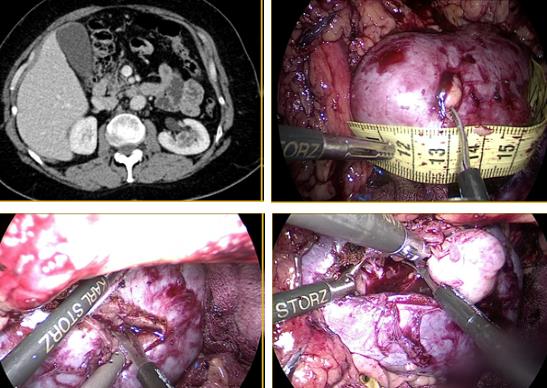

La nefrectomía radical laparoscópica en pacientes con trombo tumoral nivel I y II (T3b) es factible de realizar en manos expertas, manteniendo los principios oncológicos establecidos y la seguridad del paciente (23,24).

Inicialmente, se accede por vía transperitoneal al riñón derecho, movilizando el colon y realizando una maniobra de kocher amplia para llegar sin dificultad al hilio renal y a los grandes vasos. Se debe disecar al vena cava por encima y por debajo del hilio renal, especialmente en su cara posterior. De manera habitual, se controlan y seccionan las arterias renales.

Posteriormente, con pinzas atraumáticas se evalúa la posición del trombo en la cava. Se introduce una pinza Satinsky laparoscópica y se pinza parcialmente la vena cava, incluyendo el trombo. Esta maniobra evita el sangrado retrógrado por las venas lumbares que se produce al pinzar la cava en sus puntos distal y proximal a la afluencia de la vena renal. Se liga y secciona la vena renal, para tener mayor maniobrabilidad en el manejo de la vena cava. Se completa la disección de la pieza quirúrgica para tener mayor comodidad en la trombectomía. Luego, se efectúa la cavotomía con tijera fría y se extrae trombo. Finalmente, se sutura vena cava con polipropileno 4/0 y se comprueba hermeticidad (Figura 23).

Quienes hemos tenido la experiencia de operar tumores renales con trombos en la cava, hemos sufrido el sangrado que se produce al no tener controladas las venas lumbares. Con trombos hasta nivel II (clasificación de Novick)(25) es posible realizar este procedimiento en forma segura cuando se cuenta con pinzas Satinsky laparoscópicas, disponibles en el mercado. Cuando no se cuenta con estos elementos o el trombo sobrepasa este nivel, es preferible hacer una cirugía abierta.